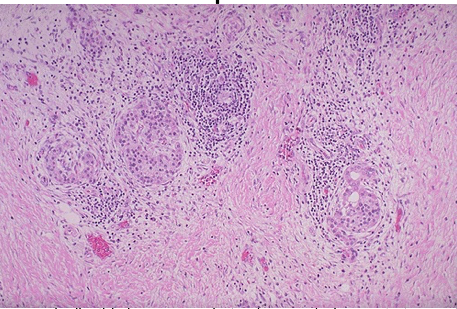

What type of pancreatitis?

Chronic

oRecurrent, progressive pancreatic tissue destruction

o Alcohol abuse is major cause

o Chronic inflammation, fibrosis, calcification

o Pancreatic insufficiency w/ malabsorption and/or diabetes

o 3-4% mortality/year